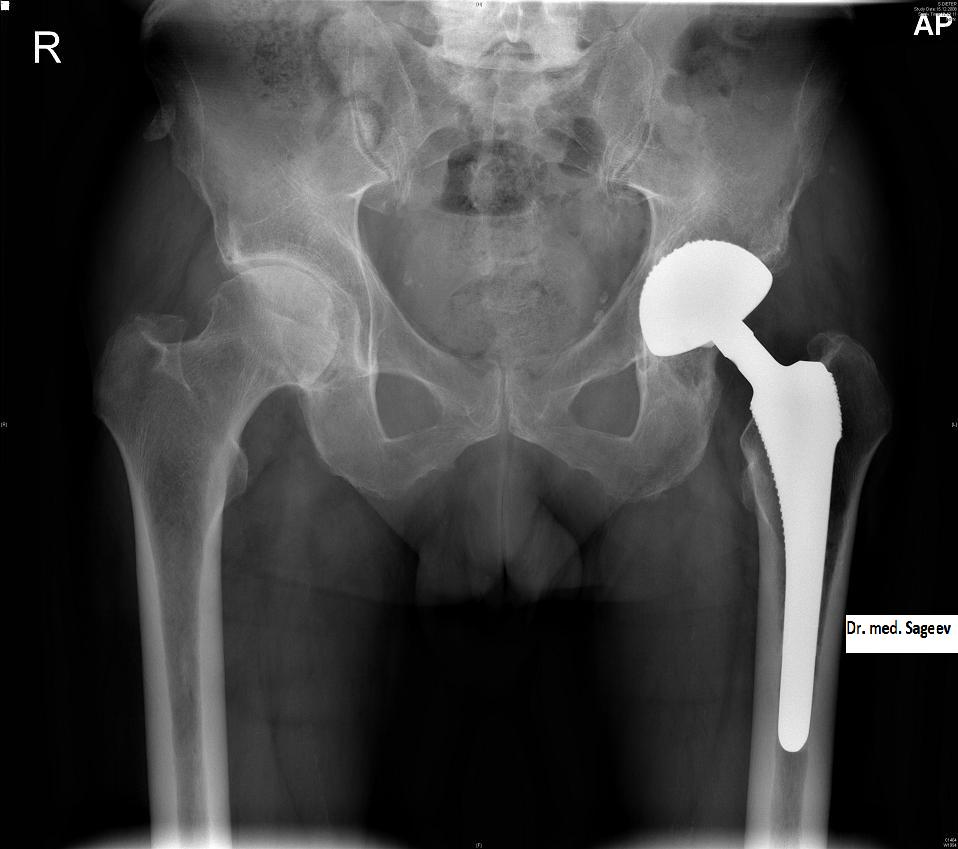

"ломает пожилой человек шейку бедра (самая распространенная травма) – это на 150 тысяч минимум он уже попал"

Понятно, что расходы у пациентов вырастут очень серьезно. Вот схватило у человека спину. Надо снять боль, провести диагностику, физиотерапию, мануальную терапию. За все про все – выйдет тысяч 30. А если, не дай бог нужна операция – то на порядок больше. Эндопротезирование тазобедренного сустава, допустим – от 150 до 300 тысяч, в зависимости от стоимости протеза. То есть ломает пожилой человек шейку бедра (самая распространенная травма) – это на 150 тысяч минимум он уже попал. Или поиграл в футбол, травмировал мениск или связку в колене – от 50 до 150 тысяч. Это не считая реабилитации. Нужна лечебная физкультура, ортопедические устройства на сустав и т.д.